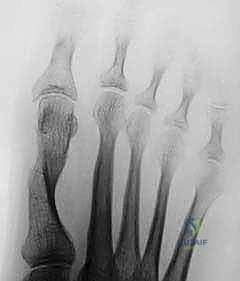

Figure 2A: Intraoperative radiographic appearance of the osteotomy. The “medial bump” still needs removal from the metatarsal.